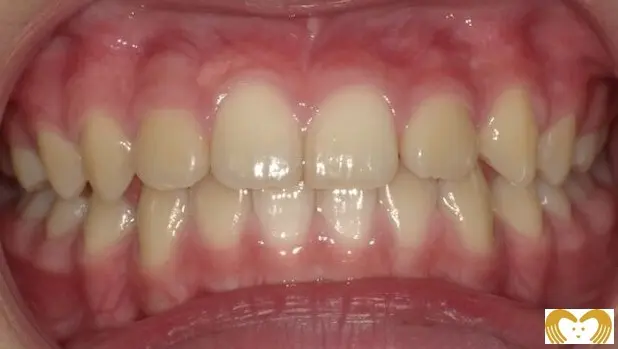

症例02:交叉咬合

《Before》

《After》

- 年齢:

- 7~12歳

- 性別:

- 女の子

- 治療内容:

- ネオキャップシステムによる、交叉咬合の治療

- 治療回数・期間:

- 約5年間

- 治療費:

- 495,000円(税込)

- リスク:

- 取り外し可能な装置の為、治療の効果が使用頻度に左右されます。